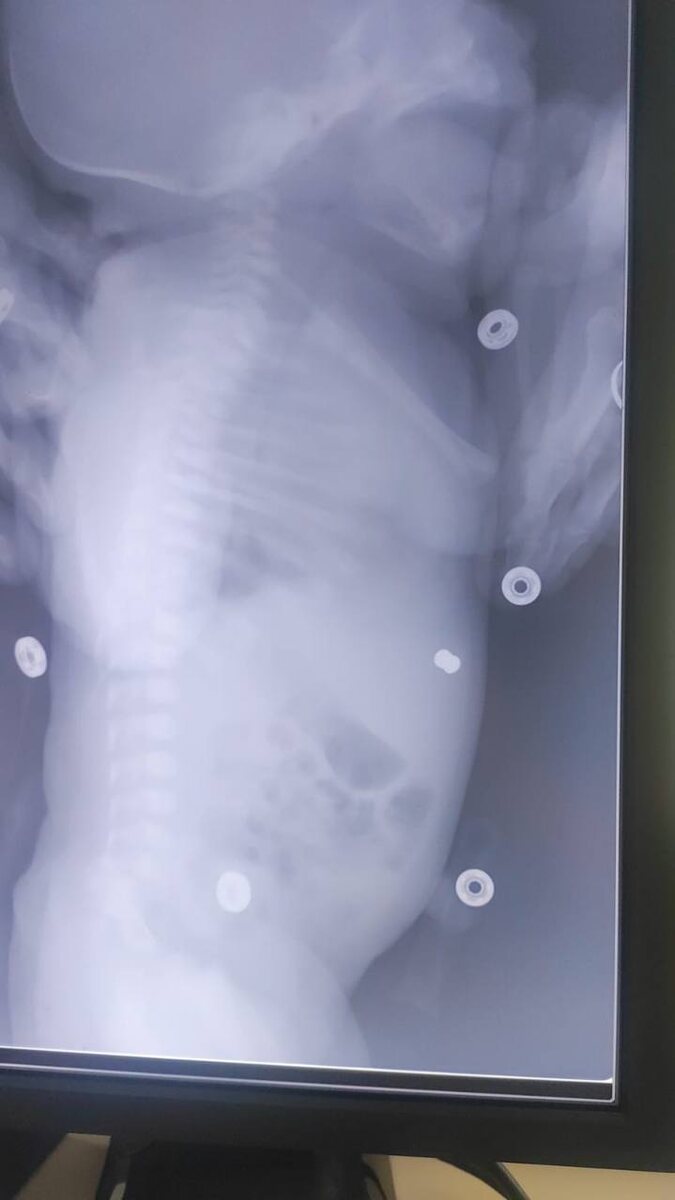

Вечером в пятницу, доставили ребенка из роддома с инородным телом мягких тканей передней поверхности грудной клетки, в стабильном состоянии. Оказалось, что ещё на 30 неделе внутриутробного развития, ребенок получил пулевое ранение от своего отца, который во дворе тренировался с пневматическим ружьем и рикошетом пуля отлетела прямо матери в живот. Пройдя кожный покров, матку, окоплодный пузырь снаряд застрял в подкожно-жировой клетчатке ребенка. Роды прошли успешно. После полного обследования, ребенка прооперировали и удалили инородное тело. На момент написания статьи ребенку уже больше 2-х лет, живет и развивается по возрасту!